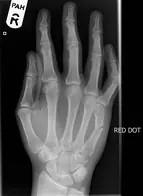

Main

Fracture de metacarpien

Fractures de phalanges

Fractures/entorses os du carpe